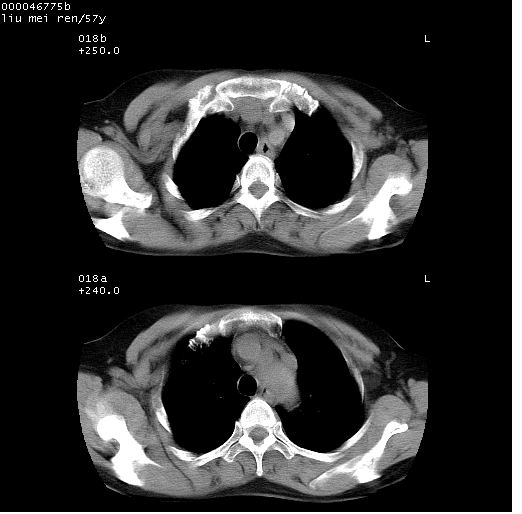

患者 女,57岁。因车祸受伤,其家属要求行“全身ct检查”。平素健康。

胸部ct轴位平扫(层厚10mm,螺距1.5,重建间隔10mm),图像如下:

左位上腔静脉,先天变异。

左位上腔静脉,先天变异。与双侧上腔静脉区别。